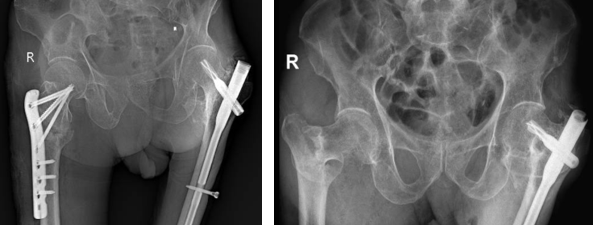

• Phương pháp kết hợp xương bằng đóng đinh nội tuỷ: Phương pháp này được chỉ định cho những trường hợp gãy xương phức tạp, gãy không vững và có thêm mảnh rời. Cụ thể, một số loại đinh nội tủy được sử dụng phổ biến gồm: Gamma, PFNA​​​​​​​

Đinh nội tuỷ PFNA

• Phương pháp kết hợp xương bằng nẹp vít: Phương pháp này được chỉ định cho trường hợp gãy xương đơn giản. Các loại nẹp được sử dụng phổ biến gồm: nẹp khóa đầu trên xương đùi, nẹp gấp góc DHS …​​​​​​​

Nẹp DHS

Nẹp khoá đầu trên xương đùi